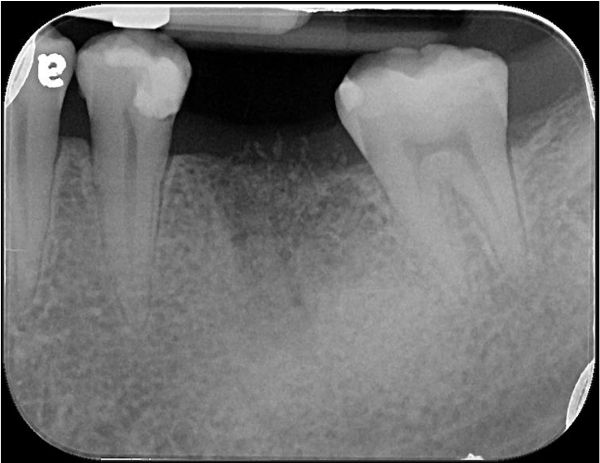

治療前,左下第一大臼齒根尖病變

根尖病變

電腦斷層確認根尖病變

6個月後骨癒合